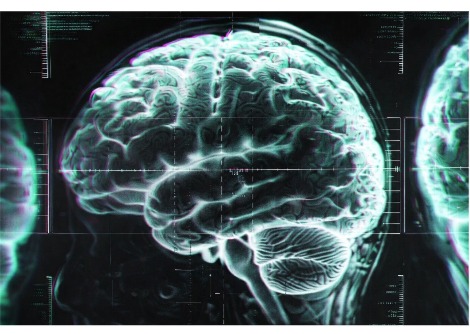

من وجهة النظر السريرية ، زاد الأداء المعرفي في 6 من 7 مرضى مع تمثيل ثلاثي الأبعاد أفضل ، وفهم أفضل للتعليمات ، وتحسين التفكير ، والانتباه ، والذاكرة العرضية. ومع ذلك ، لم يكن للعلاج تأثير على القدرة على الشم. تم تأكيد هذه التدابير لتحسين الوظائف المعرفية من خلال تصوير الدماغ الذي أجراه قسم CHUV لعلوم الأعصاب السريرية ، والذي كشف عن زيادة كبيرة في الاتصال الوظيفي.

تشير هذه البيانات إلى أن العلاج يعمل على الدماغ من خلال تقوية الاتصال بين مناطق معينة من القشرة. يوضح بريفو: "يبدو أن الحفاظ على نظام GnRH يلعب دورًا رئيسيًا في نضوج الدماغ والوظائف المعرفية". ويضيف بيتلود: "في متلازمة داون ، يبدو علاج GnRH النابض واعدًا ، لا سيما أنه علاج حالي ليس له آثار جانبية كبيرة".